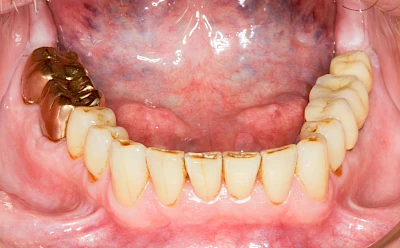

Fehlen einzelne Zähne und die Nachbarzähne sind unbeschadet oder gut zahnärztlich versorgt, werden immer häufiger Implantate gewählt, um die Lücken zu schließen. Auch bei größeren oder verteilten Lücken, wenn keine herausnehmbare Prothese gewünscht ist, werden Implantate für Kronen- bzw. Brückenversorgungen gesetzt. In Einzelfällen entscheiden sich sogar zahnlose Patienten für eine festsitzende Versorgung auf Implantaten.

Varianten zur Verankerung von festsitzendem Zahnersatz auf Implantaten

Neben rein implantat-getragenen zahnärztlichen Versorgungen werden bei herausnehmbaren Prothesen Implantate auch in Sinne einer "strategischen Pfeilervermehrung" ergänzend zu eigenen Zähnen zur Verankerung eines Zahnersatzes genutzt.